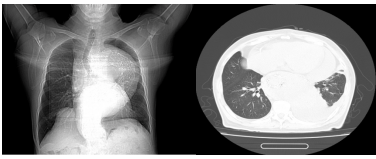

一位尚未透析的终末期肾脏病患者

也就是我们常说的“围透析期”,通常发生在刚开始透析,或者透析不充分的患者身上透析不充分,我们图中第二例患者就是一位未及时开始透析的终末期透析患者。如果透析次数不够、时间不足,毒素清除得不够理想,依然会持续刺激心包。